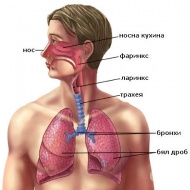

S11.0 Открита рана, обхващаща ларинкса и трахеята

Наранявания на ларинкса и трахеята, в резултат от травми са доста необичайни. Епидемиологичната хара...